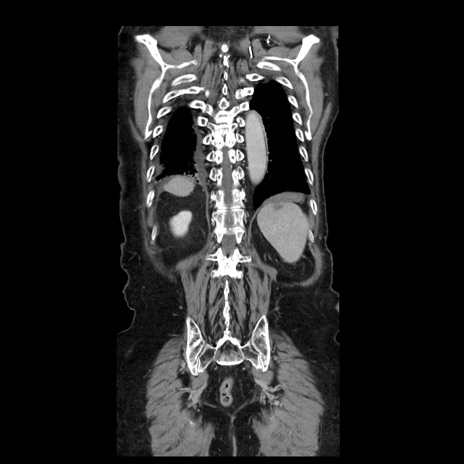

症例21(冠状断像)

【症例】70歳代男性

【主訴】腹痛

【現病歴】肝硬変・肝細胞癌にてかかりつけの方。約9時間前に食後より腹痛出現。症状が徐々に増悪し、嘔吐出現したため来院。

【既往歴】肝硬変、肝細胞癌(RFA、TACE後)

【身体所見】意識清明、表情苦悶様、BT 36℃、BP 129/78mmHg、P 88bpm、SpO2 97%(RA)、右上腹部から心窩部にかけて圧痛あり、反跳痛なし、筋性防御あり。

【データ】WBC 5800、CRP 0.16